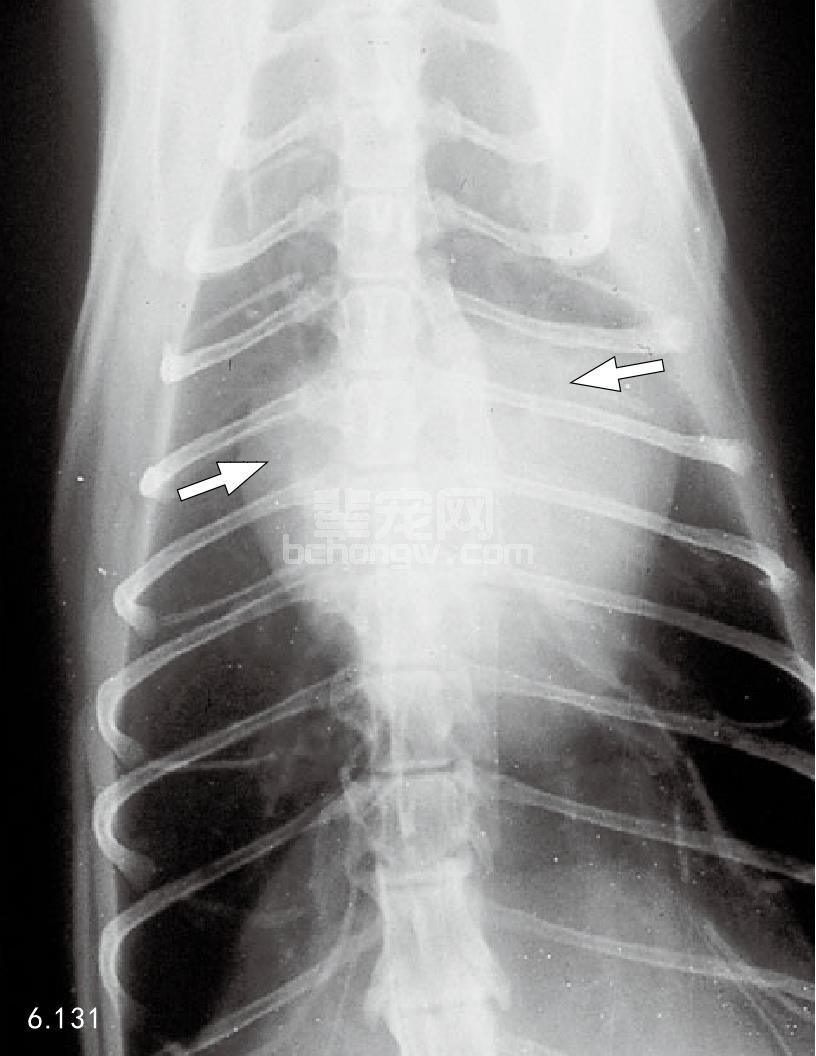

X线片 因为肥大变化是向心的,胸部X线片可能并不明显(图6.130)。由于左、右心房肥大,在腹背位 投影时心脏显现“瓦伦汀(valentine)”形状(图6.131)。这种情形可能发展到左侧或全心肌扩大症。左侧心 衰的猫常常有肺充血和组织间隙性的(而不是肺泡)肺水肿(图6.132和图6.133)。

图6.131 为图6.130所示猫的背腹位X线片。注意由于两心房的肥大(箭头)而出现的“瓦伦汀”形状。